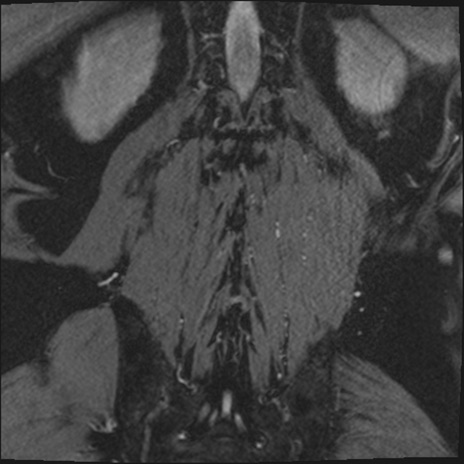

【整形】TIPS症例2 腰椎MRI 3D(冠状断像)

【症例】70歳代男性

【主訴】左下肢痛

【現病歴】2週間前くらいから腰痛、左下肢痛あり。左臀部から大腿、下腿外側のしびれが常時ある。歩行とともに同部位の痛みあり。

【身体所見】Lasegue70-/60+、Bragard-/±、PTR ±/±、ATR -/-、IP 5/5、TA 5/4、TS 5/5、EHL 右第1足趾なし/3、FHL 5/5、hypersthesia(-)、足背動脈触知良好

異常所見と診断は?